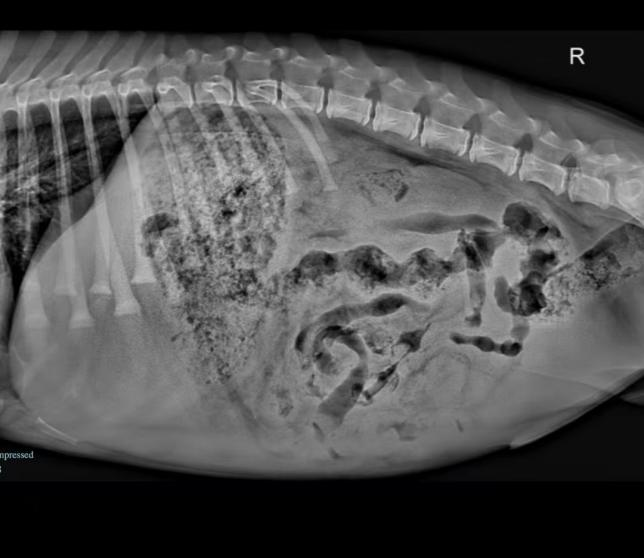

SymptomsThis 7-month-old Golden Retriever had been showing signs of vomiting and a decreased appetite for a while. Lately, the dog’s condition worsened with a sudden drop in energy, making its owner very concerned. The dog became more lethargic and weak,